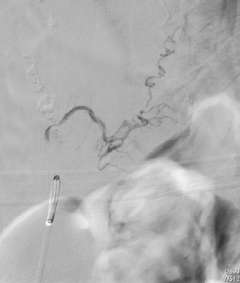

Figure 3: A palliative / partial Catheter Treatment for a Spinal AVM.

Multiple arteries feeding the spinal AVM. There are aneurysms in the feeding arteries.

Two feeding arteries harboring the aneurysms were obliterated using catheter embolization techniques.

The aneurysms were completely obliterated, and the risk of bleeding was reduced. However the AVM receives blood flow from the other feeding arteries.